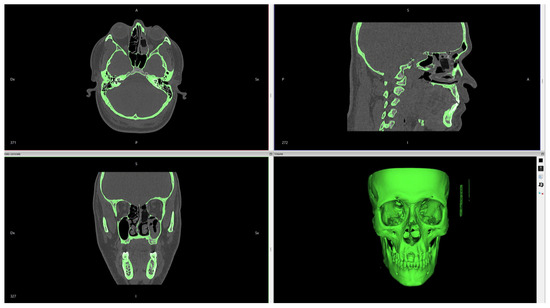

Figure 2. Invesalius software digital workflow. The imported file DICOM is transformed into a 3D image.

The workflow process is shown in Figure 2, Figure 3, Figure 4 and Figure 5.